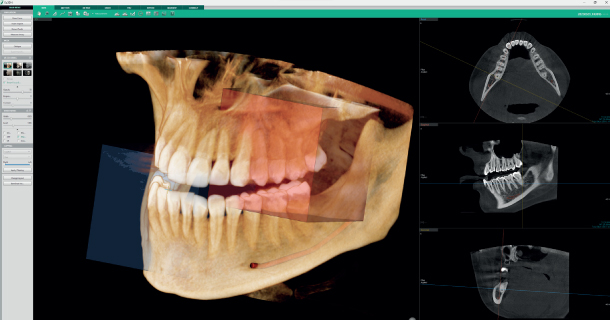

Система рентгеновской визуализации 4-в-1

1 сканирование = 5 изображений

С Green X 12 за одно сканирование вы получите 5 изображений высокого разрешения нескольких областей. Одно КТ-изображение 12х9, одну автопанораму и три КТ-изображения 4х4 повышенной четкости в выбранной области интереса.

INSIGHT 2.0 / FREE FOV

Функция Insight Pan служит для получения многослойных панорамных изображений,

гарантирующих возможность наблюдать необходимую анатомию на нужной глубине. Insight 2.0 имеет обновленную функцию свободного FOV, что позволит исследовать только интересующую область